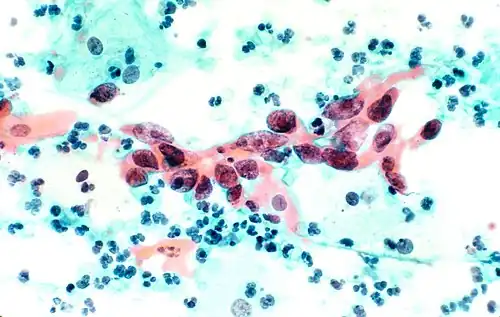

В результате окрашивания по Папаниколау клетки остаются прозрачными. Ядра клеток принимают цвет от синего до чёрного. Цитоплазма окрашивается в сине-зеленый цвет; кератин — в оранжевый.

Эозин Y окрашивает поверхностный плоский эпителий, ядрышки, реснички и эритроциты. Светло-зеленый SF желтоватый придает голубое окрашивание цитоплазме призматических, парабазальных плоских и промежуточных плоских клеток. Поверхностные клетки окрашиваются от оранжевого до розового, а промежуточные и парабазальные клетки становятся бирюзово-зелеными или голубыми[6].

Плоскоклеточная карцинома, бронхоальвеолярный лаваж.

Клетки меланомы, тонкоигольная аспирационная пункционная биопсия печени.